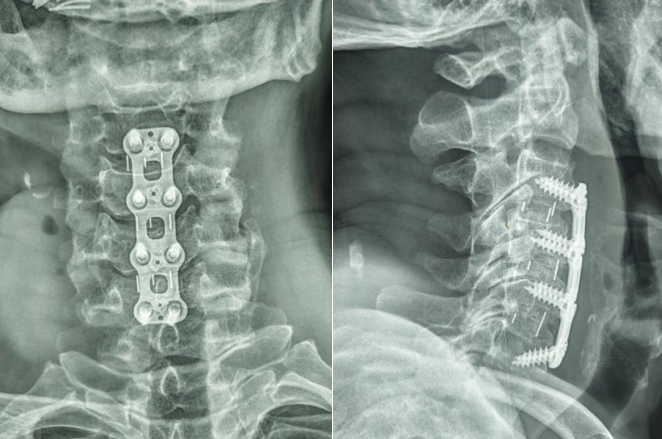

大竹县人民医院通过多节段颈椎ACDF手术成功救治颈脊髓损伤伴不全瘫痪患者

近日,大竹县人民医院骨科团队顺利完成了一例多节段颈椎ACDF手术,手术全程仅用2.5小时,顺利救治了一名因颈脊髓损伤伴不全瘫痪的患者。

据悉,患者肖某现年75岁,“颈部摔伤伴四肢麻木乏力3小时”入院入院时四肢肌力明显减弱约2级,感觉麻木,痛觉减退,呈不全瘫痪状态,经检查诊断:1颈脊髓损伤伴不全瘫痪;2、颈椎间盘突出伴椎管狭窄。颈脊髓损伤是一种非常严重的损伤,造成患者死亡或残疾的几率较大,为挽救患者生命,骨科团队根据患者情况,为患者制定了“多节段颈椎ACDF手术”的方案。经术前充分准备骨科团队通过紧密协作,仅用2.5小时顺利完成多节段颈椎ACDF手术。术后在护理团队的精心护理下患者恢复良好,目前四肢肌力达4级,麻木减退,已能够逐渐下床行走。

相关科普:颈椎前路椎间盘切除减压植骨融合术(ACDF)是颈椎前路减压融合术(ADF)的一种,具有临床疗效显著,创伤小、出血少、并发症少等优点。与后路手术相比,前路手术可以直接解除来自脊髓前方的压迫因素,如退变的椎间盘组织、椎体后缘骨赘、肥厚或骨化的后纵韧带以及增生的钩椎关节等;椎间隙植骨可有效恢复椎间隙高度、维持颈椎的生理曲度、重建病变节段的稳定性,符合颈椎的病理生理特点,一直是治疗颈椎疾患的主流术式。ACDF手术适用于:有脊髓受压症状的脊髓型颈椎病、颈椎间盘突出症、后纵韧带骨化症(孤立型);神经根型颈椎病,经保守治疗无效,症状严重,反复发作;以间盘突出为主的脊髓型和神经根型颈椎病,一般病变小于三个节段;椎间不稳伴有神经症状需要固定者;椎体前缘骨质增生压迫食管者。